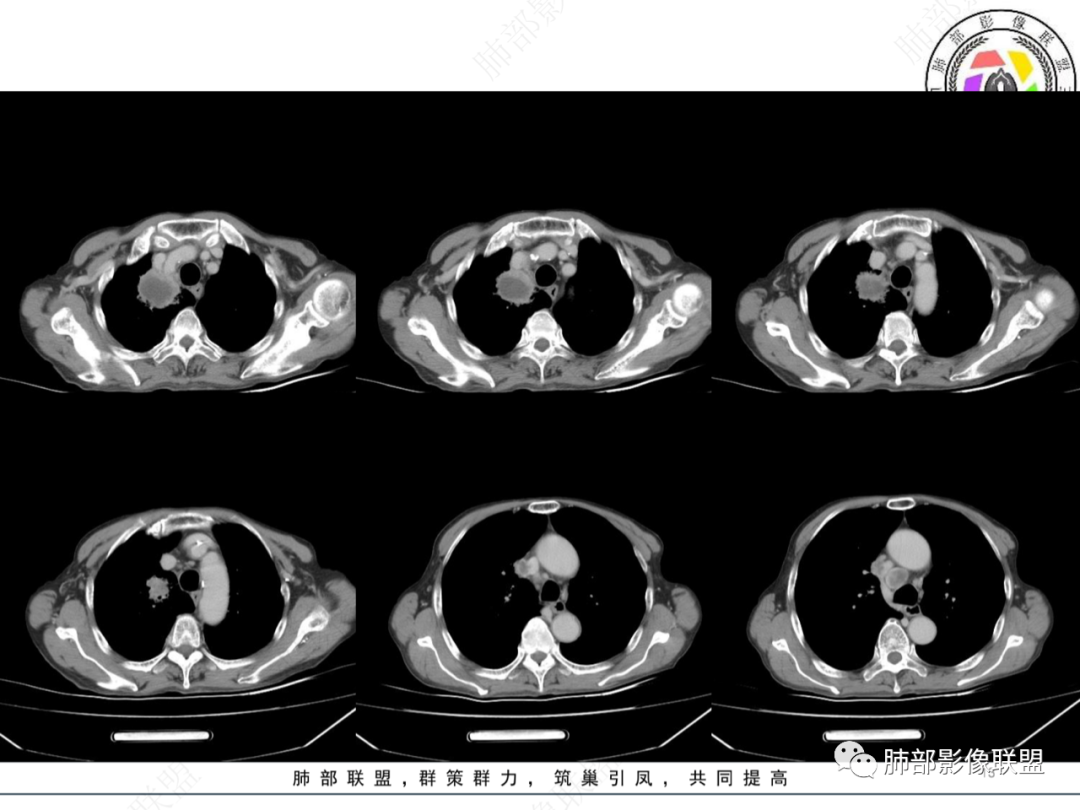

最让人忐忑的:淋巴结

炎性:结核多见,肿瘤:鳞癌多见

最让人放心不下的是这里

南边  :

上腔静脉外面按理没有淋巴结啊

其次:团块影的壁:厚薄不均匀

从上面的图看:炎性肯定有

癌?结核?不能排除

1月后,发热再次入院

这些新发的

合并有胸水

出现液气平面

治疗一周后复查

周围干净了,液平小了

壁似乎均匀了

可惜没薄层

窗宽不够窄

看不太清

治疗两周,病灶内气体没了

就目测看内壁还是清楚的